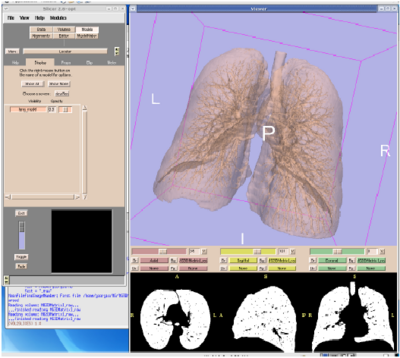

Image Registered FAST (IRFAST) for Combat Casualty Triage

Authors: Kilian Pohl in collaboration with Steve Pieper, Kirby Vosburgh, and Barnabas Takacs.

Background/Purpose: Dr. Pohl's research involves developing an automatic segmentation approach identifying major anatomical compartments from torso CT scans. Using 3D Slicer, he developed a procedure for automatically segmenting the body, bone structures, lungs, and hart from CT images (see figure). The method iterates between the identification of anatomical structures and the registration of an “atlas” to the CT data set of the subject. The atlas is based on CT data set, which we call template, and a label map that already identifies the structures of interest in the template. In the first iteration, the template with the segmentation of the body is mapped onto the CT data set of the subject. This results in a very accurate segmentation of the subject’s body. The method then combines the segmentation of the body and the CT images of the subject to identify the lungs and bone structures. In the second iteration, the method maps the atlas specific label map of body, bones, and lungs to the corresponding label map of the subject. The segmented structures are then used as a "coordinate system" used for the identification of the remaining anatomical compartments.

Grant Support: This work partially supported by SBIR SNC06C0003 TATRC/CIMIT for Image Guided FAST Ultrasound.